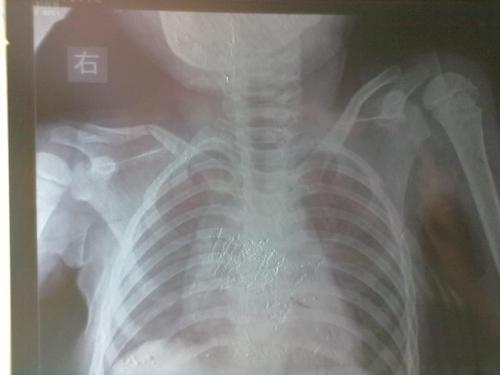

小孩锁骨骨折

11岁的,小孩锁骨断了,是保守治疗还是动手术?

儿童锁骨骨折图片

儿童锁骨青枝骨折图片

儿童锁骨骨折